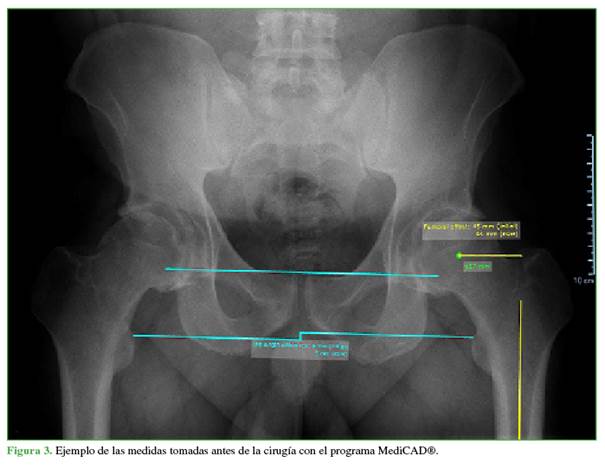

Se tomaron las mediciones en la radiografía panorámica de pelvis obtenida con el paciente de pie, antes de la cirugía y tres meses después de ella.

La discrepancia de la longitud de los miembros se midió como la distancia vertical entre la línea de referencia pélvica bilagrimal y el punto medial más prominente del trocánter menor.5 En la radiografía preoperatoria, se midió la discrepancia de la longitud con respecto al miembro inferior contrario de referencia y, en la radiografía posoperatoria, se midió la corrección real obtenida con la ATC. El resultado se registró como un valor positivo para indicar el alargamiento de la pierna operada o un valor negativo para indicar un acortamiento.

Todas las mediciones se realizaron con el programa para Windows MediCAD® (Figura 3).